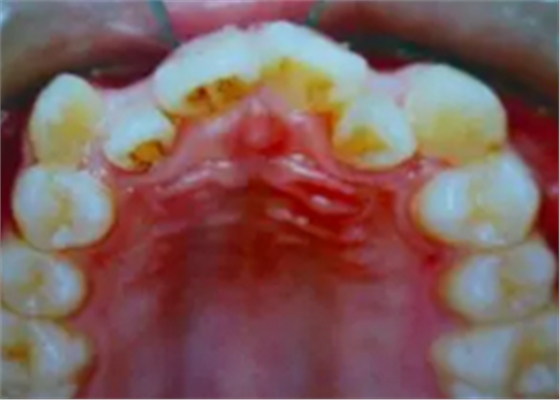

牙齒需要矯治的患者,往往牙齒和排列和咬合關(guān)系多會(huì)出現(xiàn)錯(cuò)亂,那些錯(cuò)亂的牙齒即使不拔除,它也是沒有功能的,因?yàn)樗蛯?duì)頜的牙齒咬不上。

并且,這些排列不正常的牙齒很難清理干凈,容易在它的周圍存留很多食物殘留,久而久之就形成蛀牙,最后也是一拔了之。我們醫(yī)生拔牙的時(shí)候有一定選擇的,一般是拔除那些壞牙、沒有功能的牙。